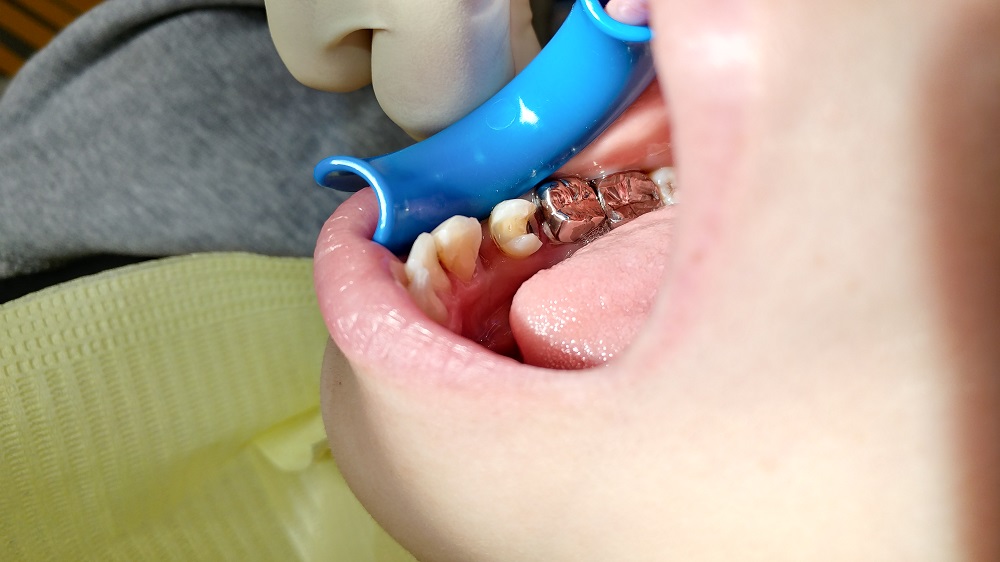

これが、抜歯した後の状態である

奥の歯には金属の詰め物(インレー)と白いレジンの詰め物が施してある

素人では判りづらいだろうが、近心側 解りやすく言えば、抜歯した1つ奥の歯の歯を抜いた側には白いセメント「レジン」が詰まっている